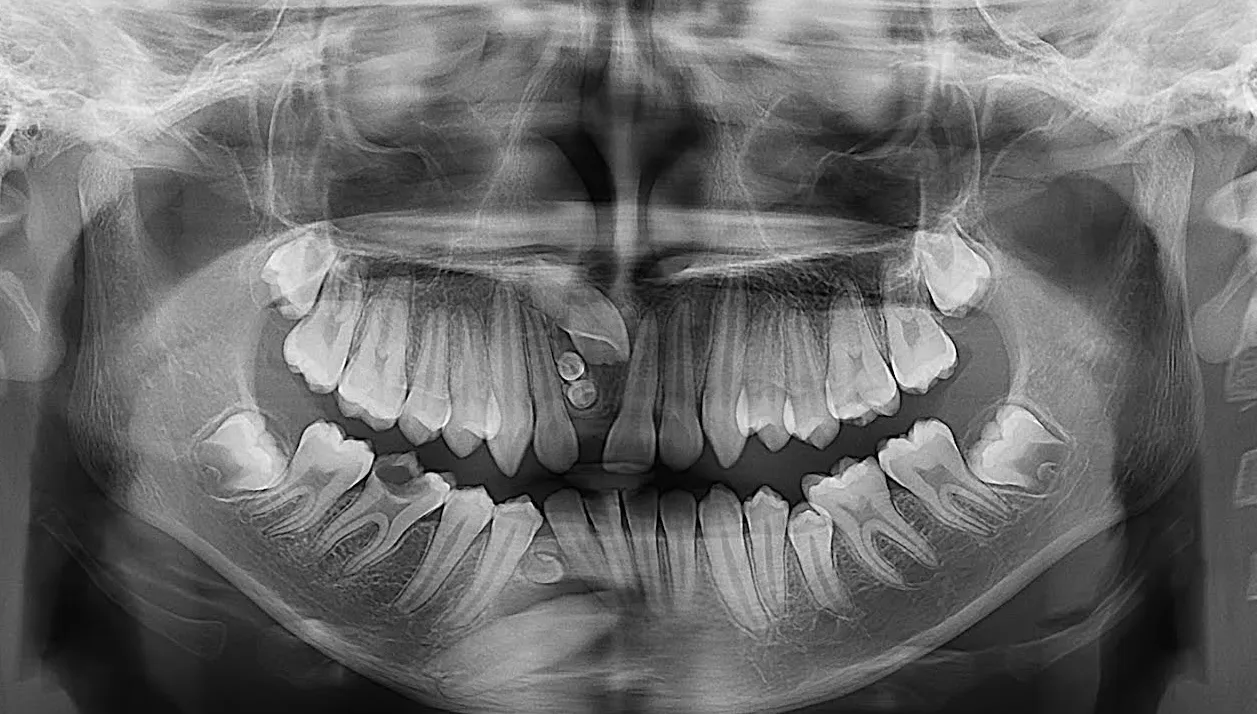

RADIOGRAFÍAS

Contamos con las siguientes radiografías:

• Radiografía Panorámica.

• Radiografía Cefalométrica Lateral.

• Radiografía ATM: Boca Cerrada / Boca Abierta.

• Radiografía Senos Paranasales.

• Radiografía Senos Maxilares (Waters).

• Radiografía Carpal.

• Radiografía Inversa de Towne.

• Radiografía Postero - Anterior (frontal).

Radiopacas intraósea

Presencia de 3 imágenes radiopacas intraósea de densidad dentaria compatible con odontomas compuestos proyectados.

• 2 en zona de pieza 11

• 1 en zona de pieza 43